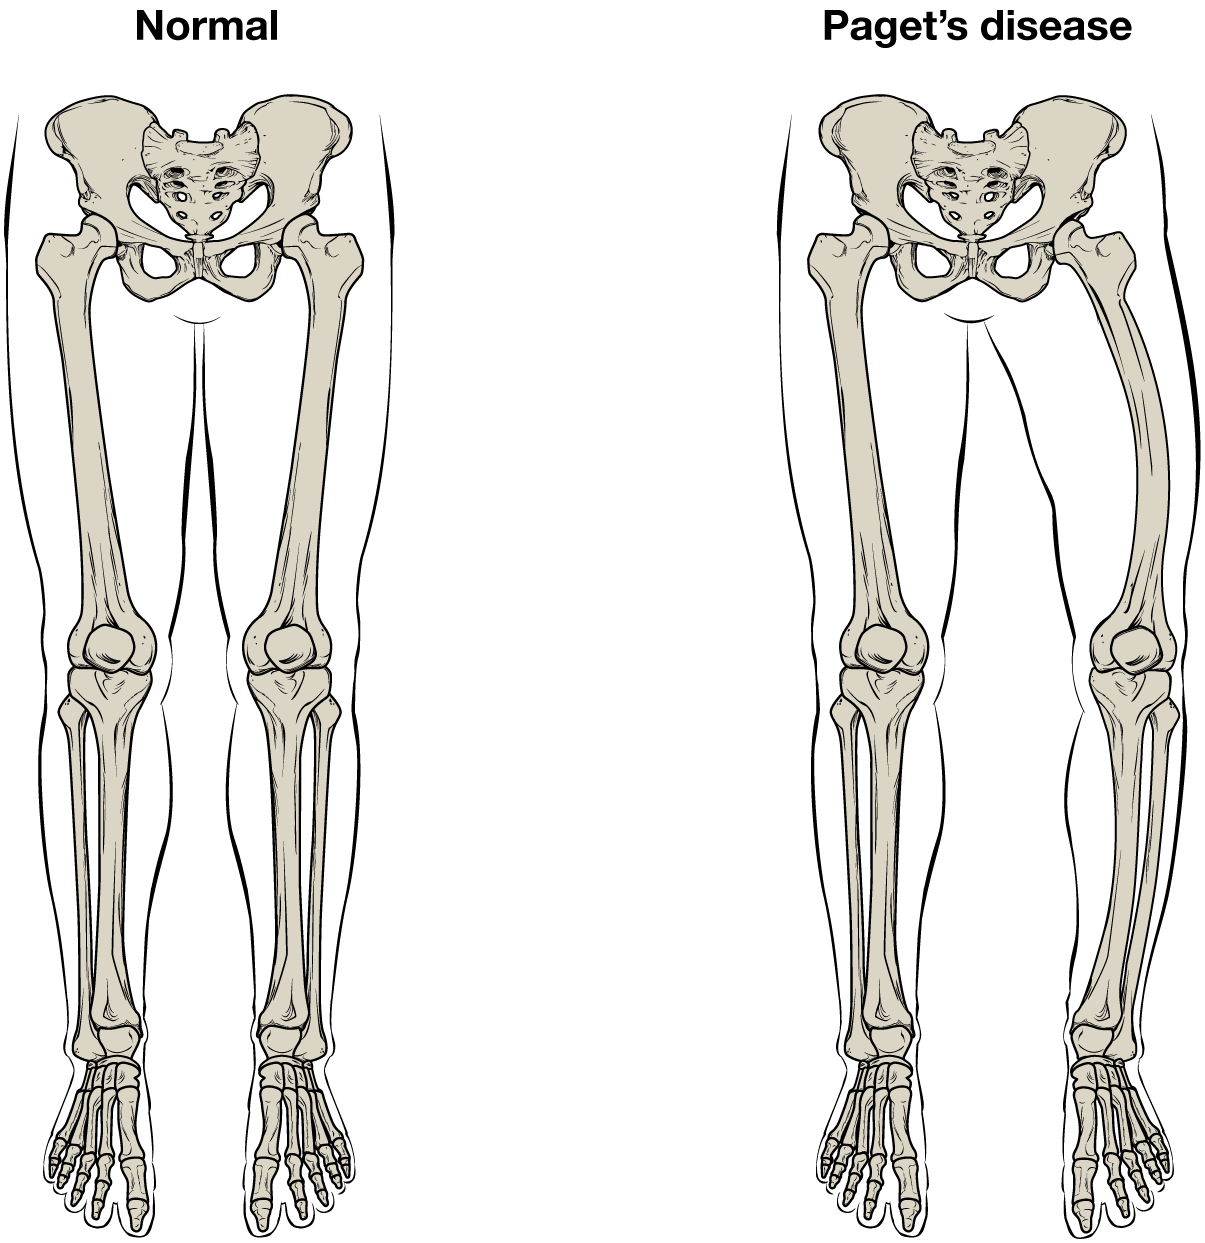

Then comes the wrist bone called the carpus the paw bone which joins the wrist and the toes known as metacarpus and then the toe bone known as the phalange. It is made up of five fused vertebral bones. The female pelvic bones are typically larger and broader than a males.

Women tend to have lighter skeleton frames than men. Together they form the part of the pelvis called the pelvic girdle. Bones are not however dead they are living tissue.